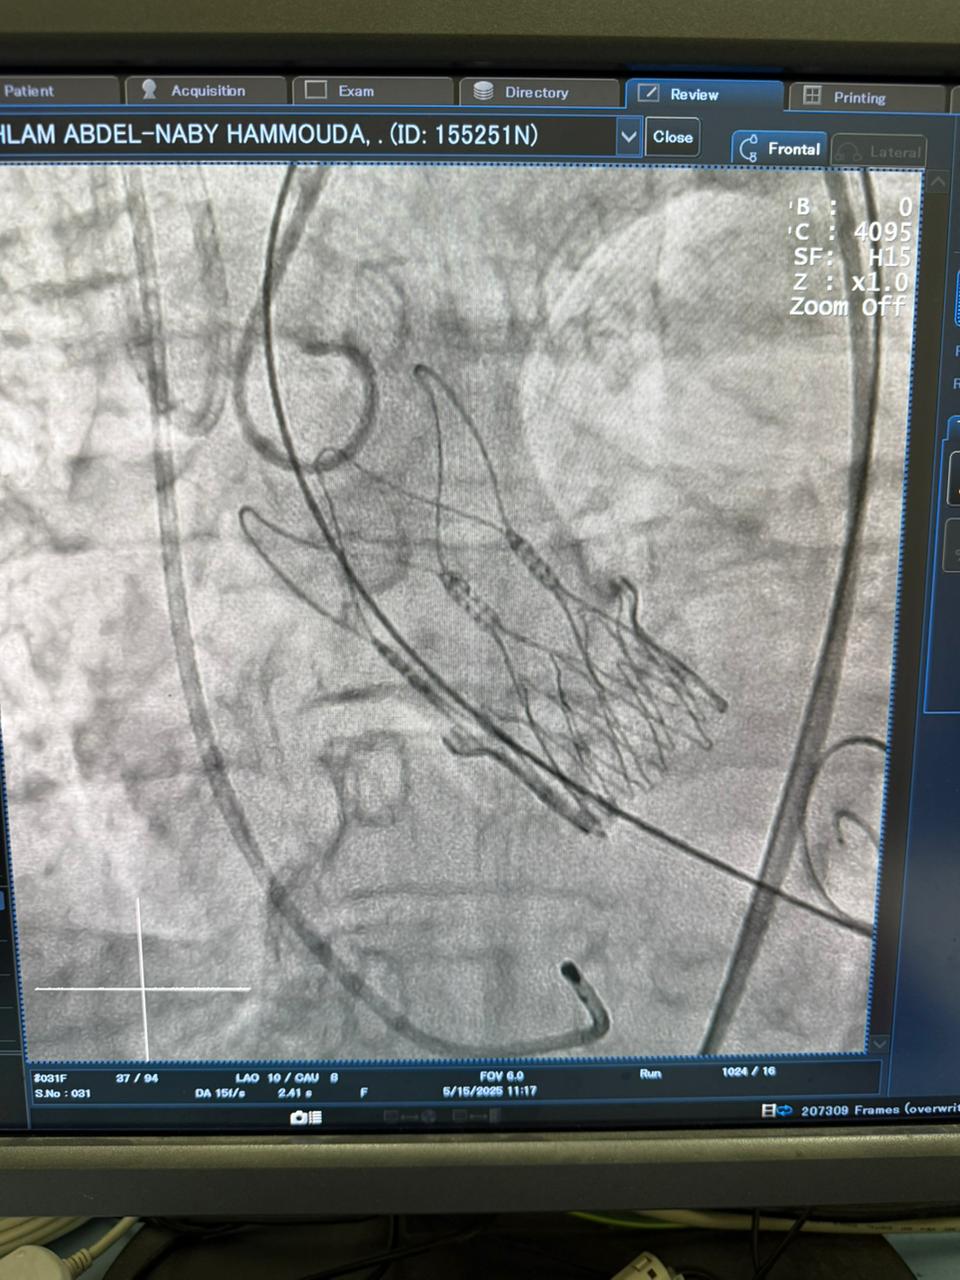

أعلنت وزارة الصحة والسكان، نجاح الفريق الطبي بأكاديمية قلب المبرة، بمستشفى مبرة مصر القديمة التابع للمؤسسة العلاجية، في زرع الصمام الأورطي بالقسطرة بواسطة تقنية (التافي) التي تعد أحدث طرق علاج ضيق الصمام بالقسطرة.

وأوضح الدكتور حسام عبدالغفار المتحدث الرسمي لوزارة الصحة والسكان، أن هذا التدخل الجراحي، كان لمريضة يتجاوز عمرها الـ70 عاما وكانت تعاني من ضيق شديد بالصمام الأورطي وتتعرض لإغماءات متكرر تهدد حياتها، مشيرا إلى أن فريق أكاديمية قلب المبرة يجري هذا التدخل الدقيق للمرة الـ52 خلال عامين، وبنسب نجاح توازي النسب العالمية.

ومن جانبه، أكد الدكتور محمد إبراهيم شقوير رئيس مجلس إدارة المؤسسة العلاجية، حرصه على تحسين الخدمات الطبية في جميع المستشفيات التابعة للمؤسسة، وإتاحة أحدث الخدمات العلاجية المتخصصة، موضحا أن هذا الإجراء تم تحت إشراف الدكتور محمد صبري رئيس قسم القلب، والدكتور أحمد السواح مدير القسطرة وهما من الخبراء معتمدون في هذا الإجراء الطبي الدقيق.